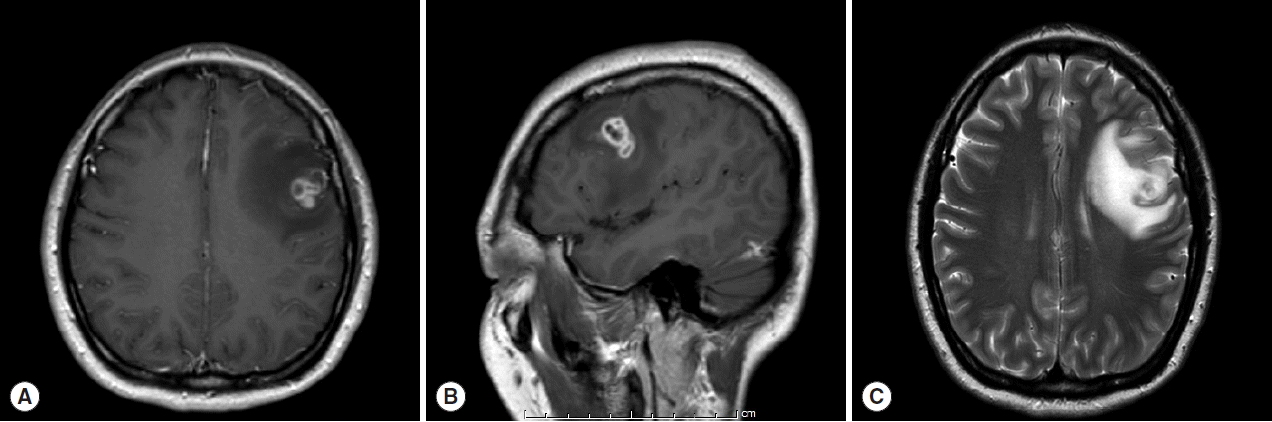

A 30-year old Thai female presented to the outpatient clinic with generalized tonic-clonic seizure 1 week ago. The duration of the seizure was less than 1 min. The patient passed out for 1 hr, and gained consciousness without memory deficit. There was no history of fever, vomiting, headache, or visual disturbances. No history of previous accident, drug allergy, or cancer was present. Her physical examination was normal. The brain MRI revealed a conglomeration of several small ring enhancing lesions of 1.9×1.4×1.6 cm in size, at the cortical posterior left middle frontal gyrus. Neither midline shift nor hydrocephalus was seen (

Fig. 1). A chest x-ray showed an unremarkable finding. No abnormal calcification was detected by plain radiograph of the femur. Routine blood examinations showed an absence of eosinophilia, and stool examinations showed no parasites.

Fig. 1MRI findings of the patient. (A) Horizontal section of T1 weighted MRI of lesion with ring enhancement. (B) Sagittal section of T1W MRI. (C) T2-weighted MRI with perilesional edema.